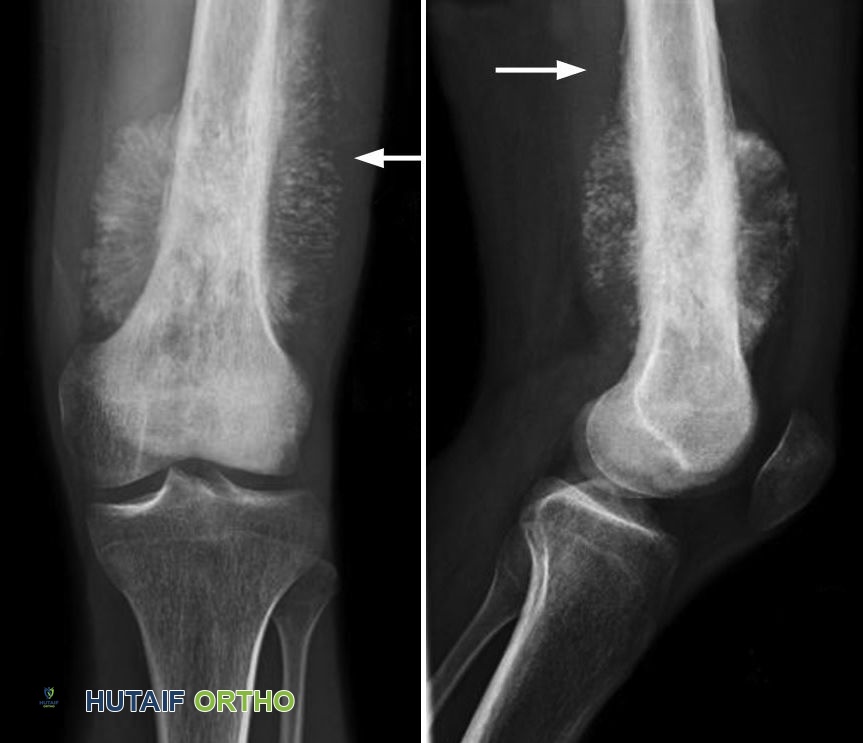

الأشعة السينية (X-rays): توفر الأشعة السينية صورًا للهياكل الكثيفة مثل العظام، وهي مفيدة جدًا في تشخيص ساركوما العظام. يمكن أن تظهر ساركوما العظام بطرق مختلفة في الأشعة السينية، ولكن النتائج النموذجية تشمل:

- تشكل عظم جديد بنمط "انفجار شمسي" (sunburst pattern).

- "تقشير البصل" (onion-skinning) - طبقات من الأنسجة على السطح الخارجي للعظم.

- مثلث كودمان (Codman triangle) - طبقات من الأنسجة على سطح العظم وتدمير عظمي.

- مظهر "سحابة الركام" (cumulus cloud) - آفة بيضاء تشبه السحابة.

(يسار) تظهر الأشعة السينية ساركوما العظام في عظم الفخذ. لاحظ تشكل عظم جديد بنمط "انفجار شمسي" نموذجي. (يمين) عند النظر إليها من الجانب، يمكن رؤية مثلث كودمان يرتفع من العظم.

بينما تظهر العديد من ساركوما العظام كآفات بانية للعظم (osteoblastic) في الأشعة السينية (أي أنها تنتج عظمًا جديدًا)، فإن النتائج الأقل شيوعًا تشمل الآفات المحللة للعظم (osteolytic) (أي أنها تحلل العظم)، أو مزيجًا من الاثنين. تظهر الآفات البانية للعظم باللون الأبيض في الأشعة السينية، بينما تظهر الآفات المحللة للعظم باللون الداكن/الأسود.